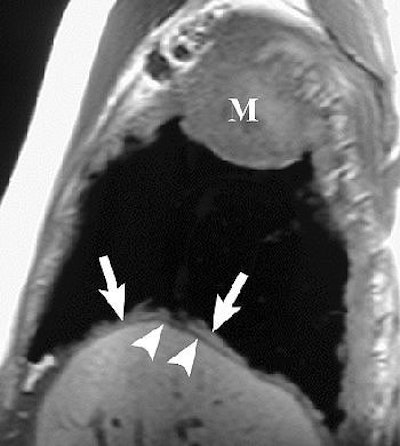

![]() |

Sagittal T1-weighted (above) and coronal T2-weighted (below) MR images show the mass with involvement of the diaphragmatic pleura (arrows). However, there is no invasion of the diaphragmatic muscle itself (arrowheads). Figure 16, Wang ZJ, Reddy GP, et al, "Malignant Pleural Mesothelioma: Evaluation with CT, MR Imaging, and PET" (RadioGraphics 2004; 24: 105-119).

On T1-weighted MR images, malignant pleural mesothelioma (MPM) is typically isointense or hyperintense. On T2-weighted images, MPM is moderately hyperintense. In both cases, gadolinium enhances the disease, they added.

MRI may also prove superior for assessing the growth of MPM, either as an invasion of the diaphragm, invasion of the endothoracic fascia, or a single chest wall focus.